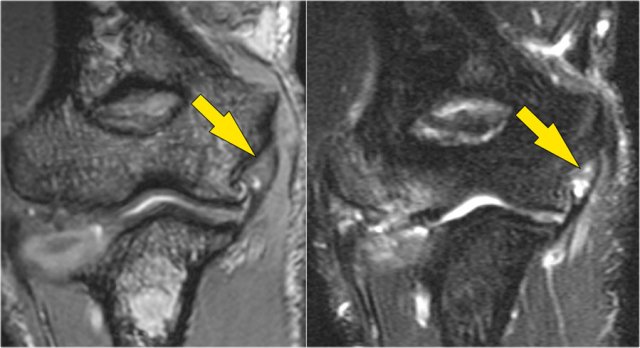

OC lesion of trochlea

These images are of a patient with anterior elbow pain.

There was no recent injury.

The clinical diagnosis was a biceps tendinitis or a bicipital bursitis.

The findings on the coronal MR-images are quite uncommon.

If you would see this in the capitellum you would call it an osteochondral lesion of the capitellum.

So this is called an osteochondral lesion of the trochlea.

Notice the small cystic changes (white arrow).

There is also a small cartilage defect.

An osteochondral lesion of the trochlea is usually seen in younger patients, who have an immature skeleton.

It is seen in the lateral trochlea like in this case due to repetitive hyperextension in an area with tenuous blood supply.

It is also seen in the medial trochlea due to laxity and posteromedial abutment.

Here a different patient.

Notice that it is a young patient, because the physis is still open.

There is a large osteochondral lesion in the lateral trochlea (yellow arrows).

Notice the edema in the subchondral bone (red arrow).

The cartilage is still intact.